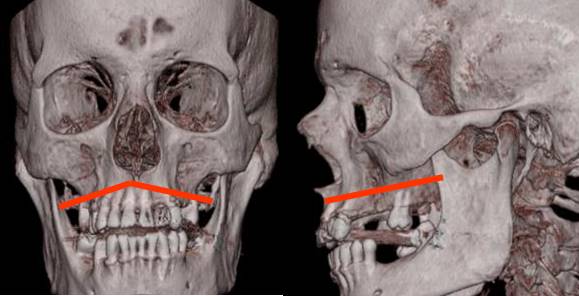

Fig 221. Diagrama de Lefort I.

Fractura horizontal del hueso maxilar.

Fig 222. Lefort I.

A y B: TAC reconstrucción coronal. Fractura lineal de la pirámide nasal izquierda en A y deprimida de la derecha en B. Adicionalmente hay múltiples fracturas orbitarias.